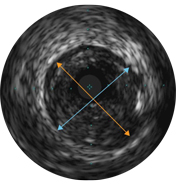

Диаметры сосудов можно определять в проксимальных и дистальных контрольных точках за счет значений диаметров просветов, средних диаметров стенок (в центральной точке между просветом и сосудом) или диаметров сосудов.

Результаты исследования ADAPT-DES показали, что ВСУЗИ было связано с выбором более длинных стентов1. ВСУЗИ помогает подтвердить области позиционирования стентов от «здоровых до здоровых» участков сосуда благодаря определению объема бляшки и типа ткани на границах поражения.

Степень раскрытия стента является предиктором тромбоза стента и рестеноза. Целевая минимальная площадь стента после ЧКВ может включать ≥ 80% референсных площадей просвета, 6 мм2 для стентов с лекарственным покрытием в сосудах, не относящихся к ЛКА, или другие критерии в зависимости от типа ЧКВ. ВСУЗИ помогает задокументировать полученные результаты2.